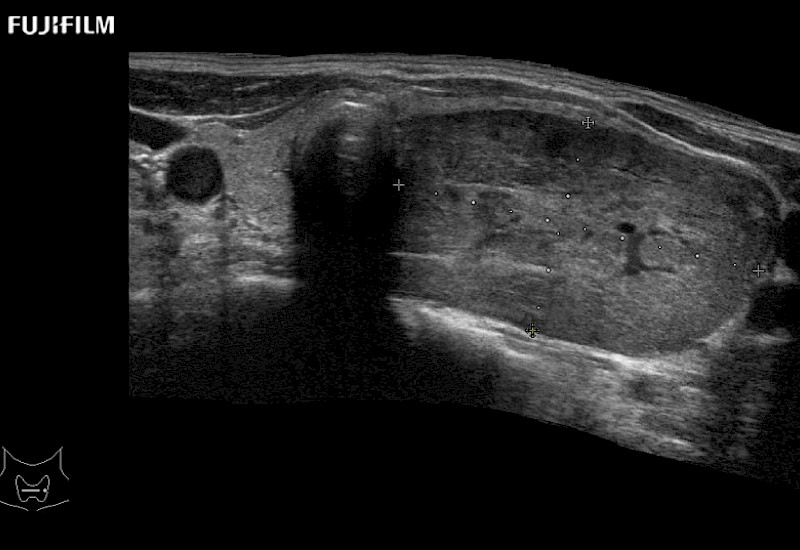

Curved array deep penetration “I” style finger-grip transducer for open surgical procedures.